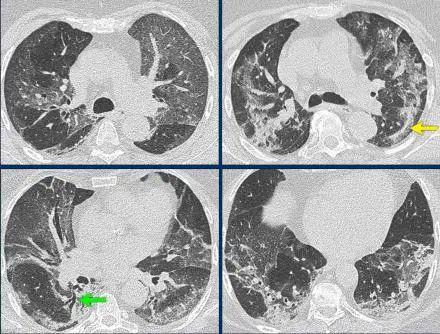

1、病原学检查中,普通发烧通过相应检测明确病因,新型冠状病毒感染主要通过核酸检测确诊,血清学检测也可辅助诊断。影像学检查上,普通发烧上呼吸道感染时胸部影像学一般无明显异常,新型冠状病毒感染患者早期胸部CT有特定表现。